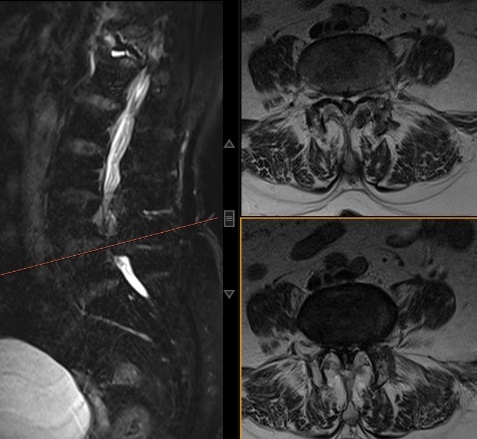

手术效果显著,家人接连求诊

赵三姐术前核磁